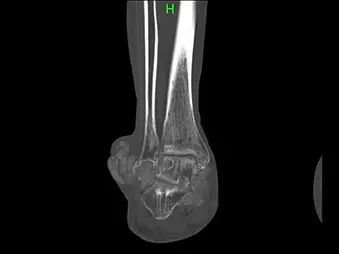

画像所見

単純X線:右足関節外果、右中指PIP関節に腫瘤陰影と骨浸食像を認める。

右足関節CT:本疾患に特徴的な、overhanging marginを認める。

単純X線ではover hanging margin徴候が特徴的で、関節内の尿酸塩結晶による炎症を繰り返し、骨内へ侵蝕することで骨膜が刺激され骨が痛風結節を取り囲むように突き出ることにより生じるとされている。また、変形性関節症とは異なり骨軟部病変があるにも関わらず、関節裂隙が保たれている場合が多く、更に骨内侵蝕もしくは骨内痛風結節では境界明瞭な長円形または円形の打ち抜き像も特徴である。MRI所見は、YuらはT2強調画像で低から中等度信号の骨破壊像を示す腫瘤を認めれば痛風結節が疑われるとし、またChenらは関節内にT2強調画像で低信号領域があり、ガドリニウム(Gd-DTPA)で周囲が不均一に増強される場合は痛風結節が示唆されると報告している。ただし、画像所見だけでは診断に至ることは困難なことが多く、最終的には病理診断により確定診断に至ることが多い。